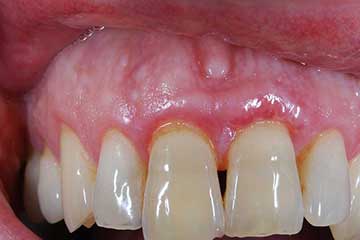

I denti irrecuperabili dell'arcata superiore ed inferiore del paziente di anni 65

sono stati sostituiti da 10 impianti, cioè protesi radicolari endo-ossee che sostengono le protesi fisse superiore ed inferiore.